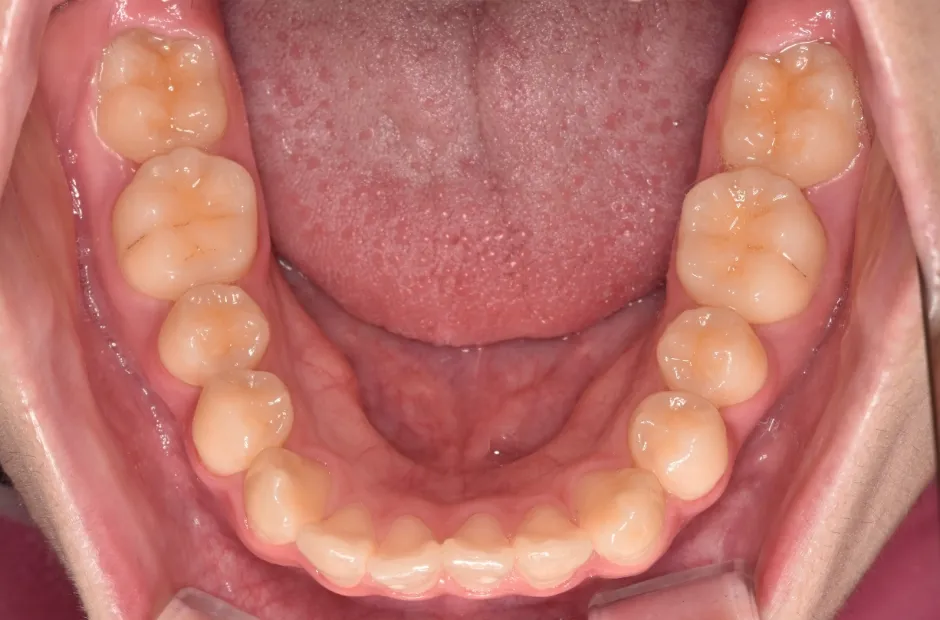

拡大床装置

叢生

| 診断名・主訴 | 叢生 |

|---|---|

| 年齢・性別 | 10歳・女性 |

| 治療期間・回数 | 2年半 |

| 治療に用いた主な装置 | 拡大床装置 |

| 抜歯部位 | なし |

| 治療費 | 30万円(税抜) |

| リスク・副作用 | 装置による違和感・疼痛・歯肉退縮・歯根吸収・虫歯のリスクなど |

治療前

治療中

治療後